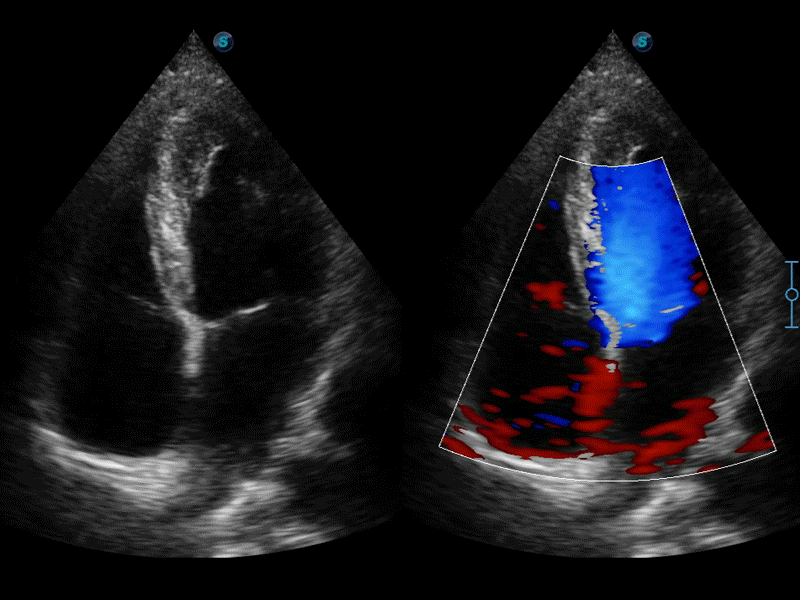

凸陣、線陣和相控陣探頭進(jìn)行實(shí)時(shí)掃描時(shí),開啟擴(kuò)展成像模式,可以擴(kuò)展超聲圖像視野,以便更完整地查看大的病灶或組織器官的解剖結(jié)構(gòu)。

通過色彩血流和實(shí)時(shí)寬景相結(jié)合,可觀察到完整的靜脈或動(dòng)脈的血流,方便醫(yī)生檢查。實(shí)時(shí)掃查過程中,如有任何操作失誤也可以很容易地進(jìn)行回掃擦除,而不會(huì)中斷掃查。